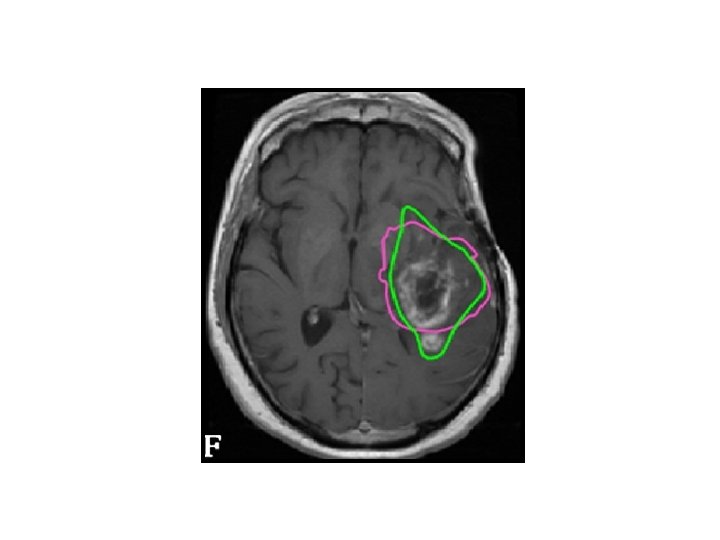

Anatomy and areas of contrast enhancement Edema

• Normal post-op changes – Enhancement – Gliosis – Oedema – Tumour bed enhancement due to high protein content – Pseudoprogression • Oedema / Infiltration - difficult to interpret the response to therapy specially after steroids.